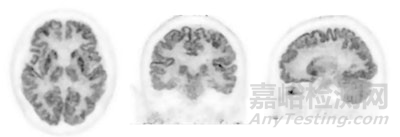

設(shè)備支持氟代脫氧葡萄糖(FDG)等放射性示蹤劑成像。近畿大學(xué)附屬醫(yī)院先進臨床醫(yī)學(xué)研究所提供的掃描圖像顯示,PositView SET-5002可同步生成水平、冠狀及矢狀三個維度的橫截面影像,幫助醫(yī)生多角度觀察病灶代謝活性。